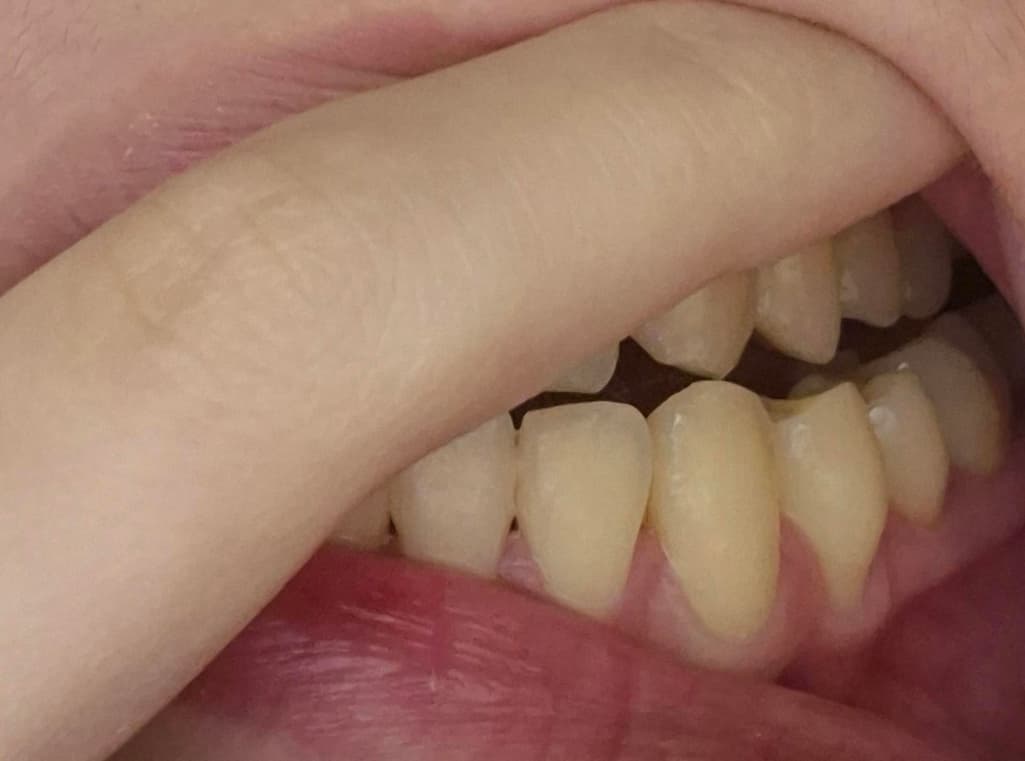

24살 여자 잇몸 퇴축이 심한 걸까요?

교정했고 24살 여자입니다..

잇몸퇴축이 너무 심한 거 같은데 치료가 필요할까요?

사진으로 봤을 경우에는 잇몸 퇴축이 조금 진행된 것으로 보입니다. 잇몸 대축은 잇몸에 너무 강한 자극이 가해지면서 생기기 때문에 양치질을 할 때 잇몸에 넘어가는 자극이 가해지지 않다고 하는 것이 좋습니다.

나이 대비하여 잇몸이 조금 퇴축된 것은 맞습니다. 지금부터 관리를 더 잘해주셔야겠습니다.

송곳니는 원래 잇몸퇴축이 다른 치아보다 먼저, 더 많이 이뤄집니다 교정 후 잇몸퇴축이 동반되는 것은 흔한 부작용 중 하나이고요 앞으로 잇몸관리 꾸준히 치과에서 받으세요